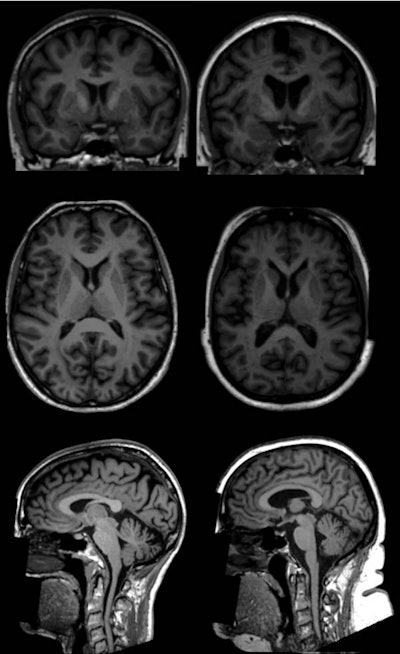

Dutch researchers investigating obesity have used MRI to link greater levels of body fat to changes in the brain's form and structure, particularly with smaller volumes of gray matter. Their study was published online on 23 April in Radiology.

To test their theory, they examined data from more than 500,000 participants in the U.K. Biobank study, which began in 2006 to learn more about the genetic and environmental factors that influence disease. From that pool, 12,087 participants with a mean age of 62 (± 7.3 years; range, 45-76 years) met the inclusion criteria. Of those subjects, 6,381 (53%) were women and 5,706 (47%) were men. Brain scans were acquired on a 3-tesla system (Magnetom Skyra, Siemens Healthineers) with a standard 32-channel radiofrequency receiver head coil.

The brain imaging protocol included 3D T1-weighted diffusion-tensor imaging (DTI), which acquired fractional anisotropy measurements to determine white-matter integrity and water molecule diffusion. In addition to total body fat calculations, volumetric measures were performed to gauge overall brain volume, gray- and white-matter volumes, subcortical gray-matter structure volumes, and regional cortical volumes.